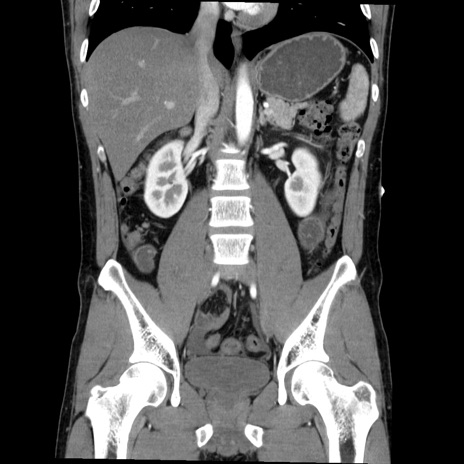

症例36(冠状断像)

【症例】20歳代 男性

【主訴】心窩部痛

【現病歴】今朝より上腹部痛あり。一旦軽快していたが再度出現したため救急要請。昨日夕に白身の魚を含む刺身を食べた。

【身体所見】BP 136/89mmHg、HR 74/min、BT 37.0℃、腹部:膨満、軟、心窩部に圧痛あり。反跳痛なし、筋性防御なし、腸雑音やや亢進あり。

【データ】WBC 17700、CRP 0.48